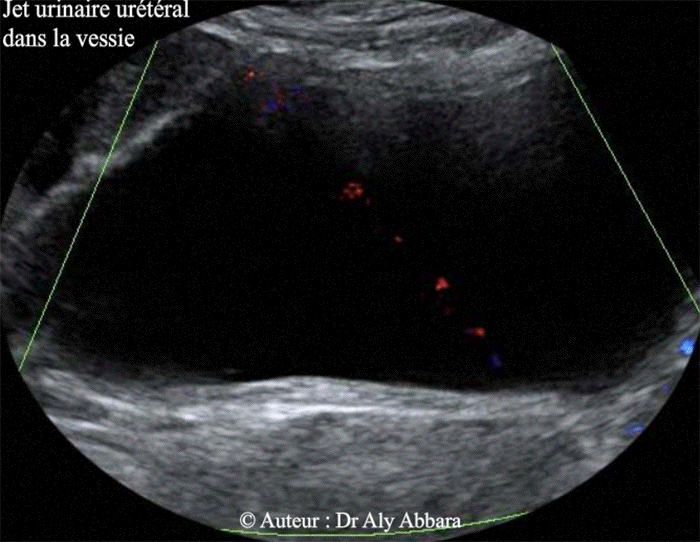

Images échographiques mettant en évidence l'aspect Doppler couleur (Dynamic-Flow) du jet urinaire urétéral (droit et gauche) dans la cavité vésicale chez une femme de 35 ans.

Ces images évoquent bien le jet du cracheur du feu !!

Voir l'aspect du jet urinaire dans la vessie en coupe sagittale médiane de la vessie